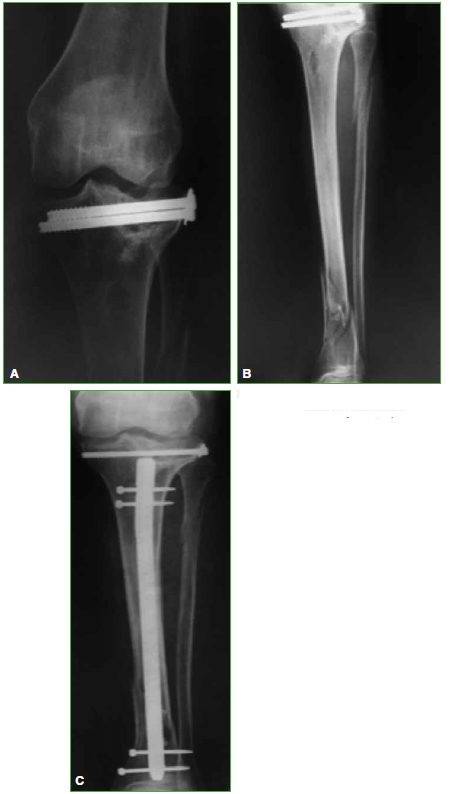

Figura. A.

Mujer con fractura de platillo tibial externo tratada con osteosintesis. B. Fractura de tibia distal, un año despues. C. Osteosintesis con clavo anterogrado endomedular de tibia.

Figura. D.

Retiro de tornillos canulados y toma de muestra, a los 4 meses. E. Artroplastia total de rodilla izquierda, con vastago tibial.

Figura. F.

Evolucion a los 7 años, sin signos de aflojamiento.